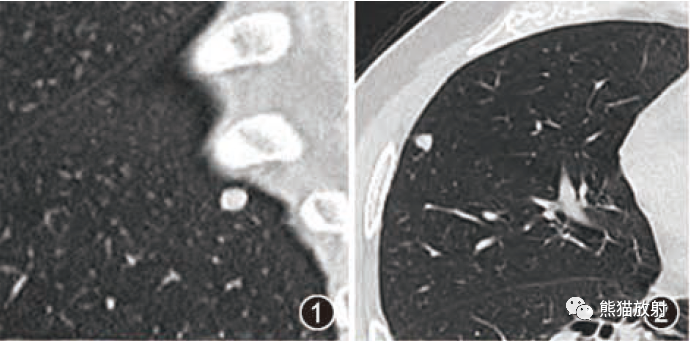

肺隔离症:易误诊为肺癌的占位性病变,肺穿刺禁忌!

肺隔离症:易误诊为肺癌的占位性病变,肺穿刺禁忌!  肺段与肺内管道应用解剖

肺段与肺内管道应用解剖  肺转移瘤的十种不典型CT表现

肺转移瘤的十种不典型CT表现  肺内淋巴结的CT表现特点及与病理对照

肺内淋巴结的CT表现特点及与病理对照  肺实变与肺不张的CT鉴别诊断